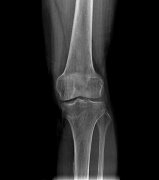

DRX光机拍四肢应该距离多少

DRX光机拍四肢时,其摄影距离(也称为焦片距)通常有一定的范围。根据公开发布的信息,四肢摄影的焦片距约为75~100cm。这个距离范围是根据X射线的穿透性和成像质量来确定的,旨在...更多 -